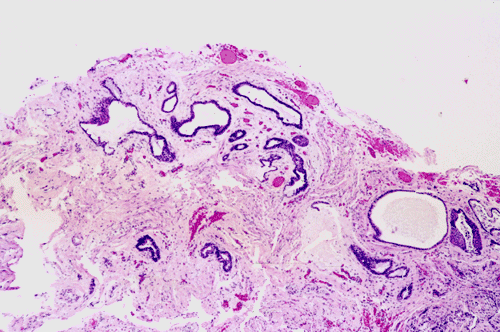

On low-magnification (Panel A),  the lesion contains has multiple glandular structures in a background of fibroconnective tissue. There is no inflammation. The epithelial component does not seem to have a complex architecture or papilla. On medium-magnification photographs (Panel B and C), the lining epithelium is low-columnar and single layered. Mucin secretion is noted on high-magnification photograph (Panel D). On intraoperative cytologic preparation (squash preparation), the single layer architecture of low-columnar cells is well appreciated (Panel E).

Macroscopically the enterogenous cysts are well delineated, thin-walled, fluid-containing masses. The cyst content varies from colorless, transparent fluid resembling CSF to milky or mucinous secretions. Histologically, the cyst is lined by a layer of bland, cuboidal to tall columnar cells with cilia and mucin production.  Enterogenous cysts have been classified by Wilkins and Odum  3 into three groups according to histological features. Type A is the simplest type; the walls of these cysts consist of a basement membrane supporting a single or pseudostratified layer of cuboidal to columnar epithelial cells with or without cilia. Type B cysts include more complex elements of the gastrointestinal tract or tracheobronchial tree, including mucus glands and smooth muscle in their wall. Type C cysts have ependymal or glial tissue in addition to the elements seen in the group B cysts. Most enterogenous cysts belong to group A or less frequently to group B.